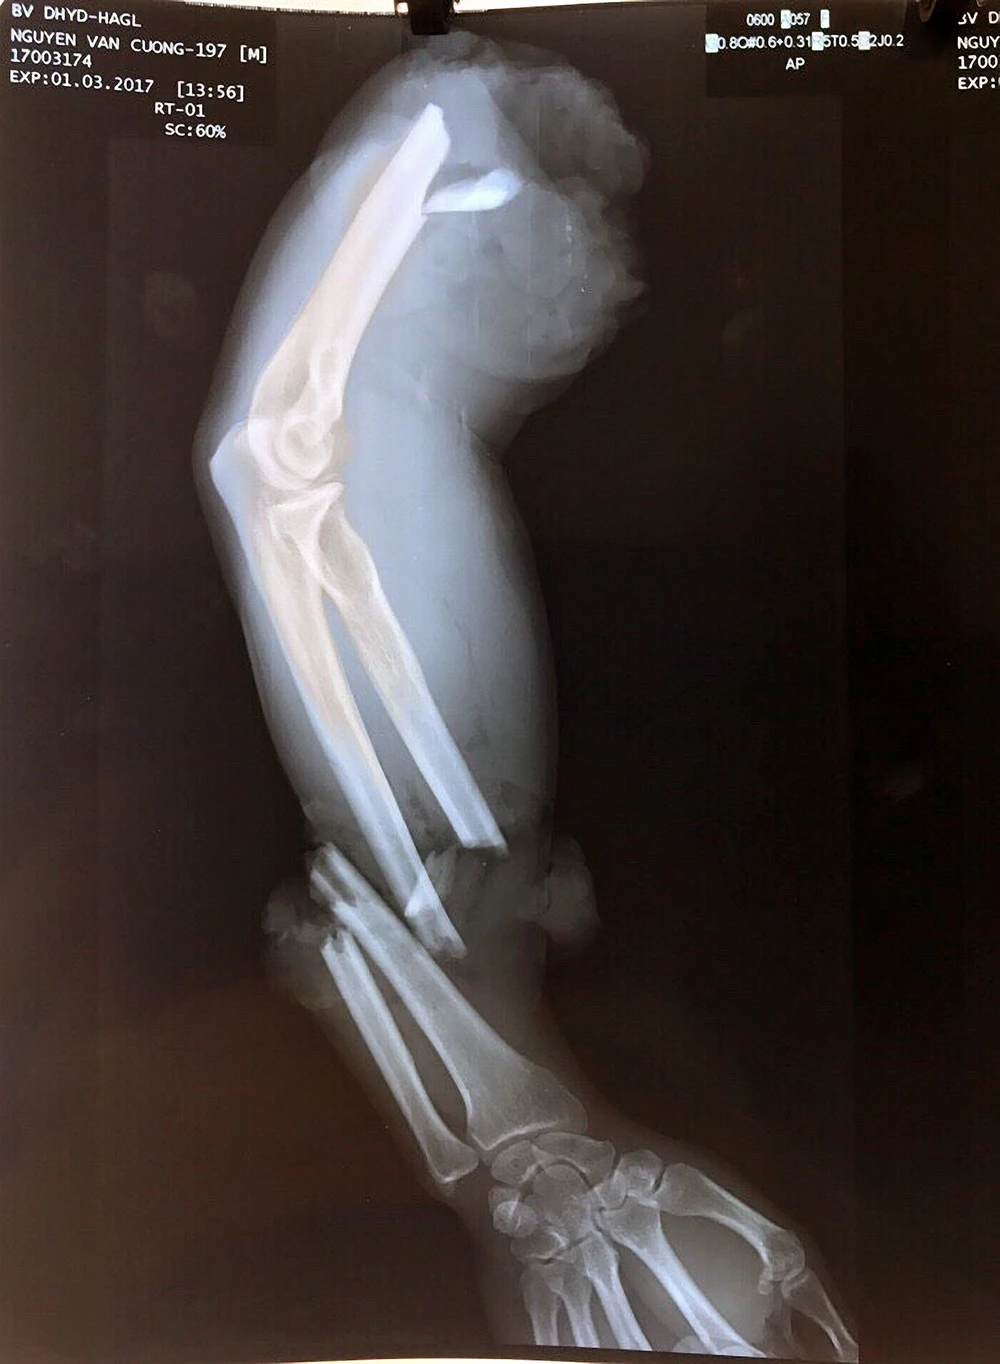

Cánh tay đứt lìa trước khi được ghép nối thành công.

BS Tuấn, người trực tiếp thực hiện ca phẫu thuật, cho biết bệnh nhân được chuyển vào viện trong tình trạng tím tái, cánh tay phải đứt lìa làm hai đoạn và dập nát.

Cánh tay đã được nối liền.

Đây là một ca nối chi rất phức tạp, bệnh viện đã phải chạy đua với thời gian để kịp thời cứu sống cánh tay đứt lìa khỏi bị hoại tử. “Sau khi chẩn đoán lâm sàng, kíp phẫu thuật đã lập tức truyền máu, thực hiện thật nhanh việc xử trí cánh tay đứt lìa, sau đó kết hợp lại xương, nối mạch máu, các dây thần kinh và gân cơ. Hiện sức khỏe của bệnh nhân đã ổn định, bệnh nhân sẽ được chuyển về TP.HCM để tiếp tục điều trị” - BS Tuấn hồ hởi kể.